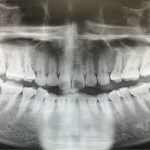

親知らずの治療例(20代 女性)_0001

レントゲンで見る親知らず